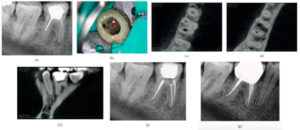

El «Área de contacto» es un término que se usa para denotar las alturas proximales del contorno de las superficies mesial y distal del diente.